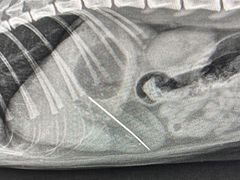

• -爱诺耐芙动物医院(万博店)

GQGQ | 23-10-07

报错